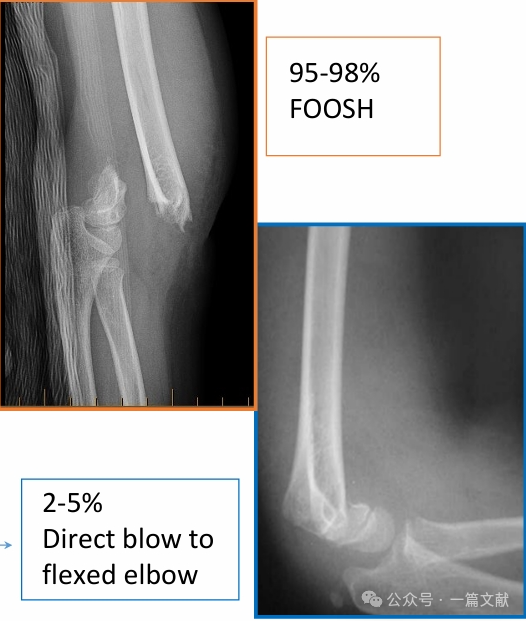

III. Fracture Types: Common extension-type and flexion-type injuries.

Extension-Type Injuries:

Flexion-Type Injuries:

* Characterized by greater overall instability and higher complication rates. May be associated with ulnar nerve symptoms.

* Treatment: Any displacement warrants closed reduction and percutaneous pinning (CRPP). These fractures have a higher rate of open reduction and percutaneous pinning compared to extension-type fractures.